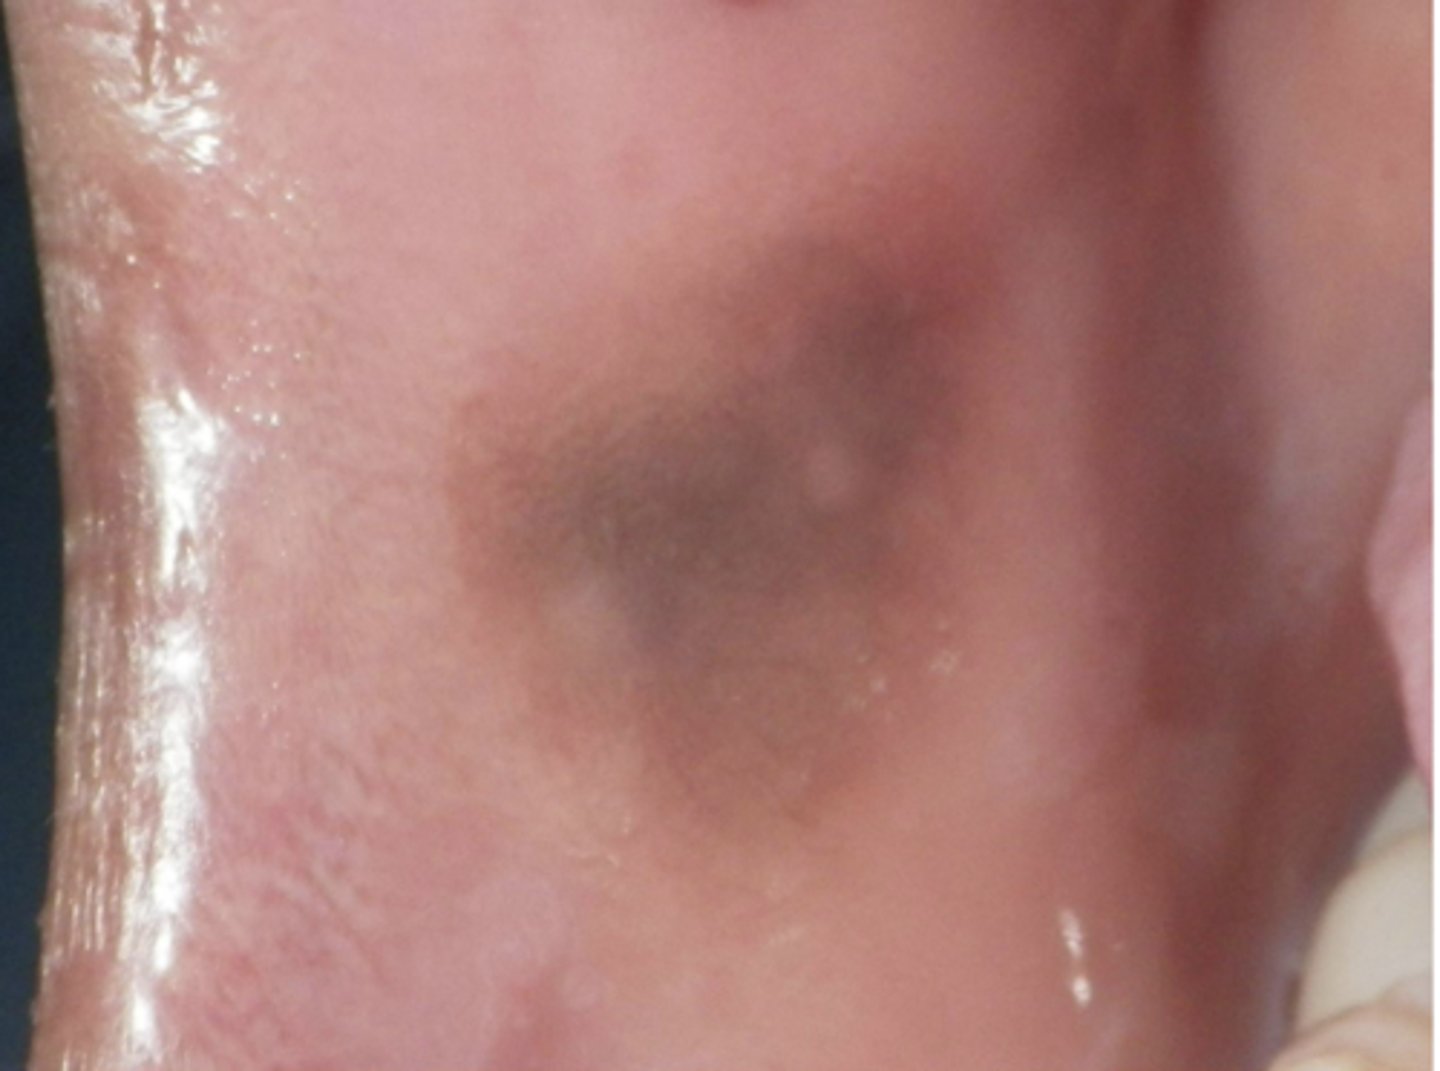

What is the differential diagnosis?

45 year-old African American female presented with this asymptomatic lesion for 2 months.

oral melanoacanthosis